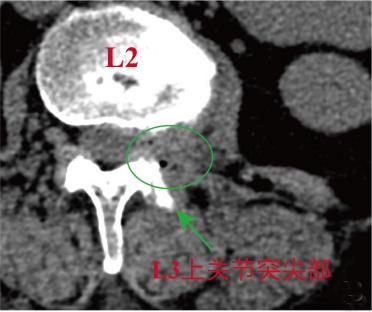

• 单通道非同轴脊柱内镜经椎间孔外入路(椎板外切迹)治疗极外侧椎间盘突出症的临床疗效观察

2026, 32(3):28-36. DOI: 10.12235/E20250050

摘要 (43) HTML (65) PDF 6.88 M (47) 评论 (0) 收藏

摘要:目的 观察单通道非同轴脊柱内镜经椎间孔外入路(椎板外切迹)治疗极外侧椎间盘突出症(FLLDH)的临床疗效。方法 回顾性分析2022年5月-2024年5月该院收治的,行单通道非同轴脊柱内镜经椎间孔外入路(椎板外切迹)治疗的FLLDH患者70例。于术前和术后,评估腰腿疼痛程度、腰椎功能和临床疗效。结果 相较于术前,术后3 d和3个月,患者下肢视觉模拟评分法(VAS)评分、腰部VAS评分、Oswestry功能障碍指数(ODI)、数字分级评分法(NRS)评分和Roland-Morris功能障碍问卷(RMDQ)评分明显降低,日本骨科协会(JOA)评分明显升高,差异均有统计学意义(P < 0.05);改良MacNab评分标准显示,末次随访时的优良率为94.28%。结论 单通道非同轴脊柱内镜经椎间孔外入路(椎板外切迹)治疗FLLDH,能明显改善患者腰腿疼痛和腰椎下肢功能,其具有创伤小、易操作、安全性高和疗效好等优点,值得在临床推广应用。